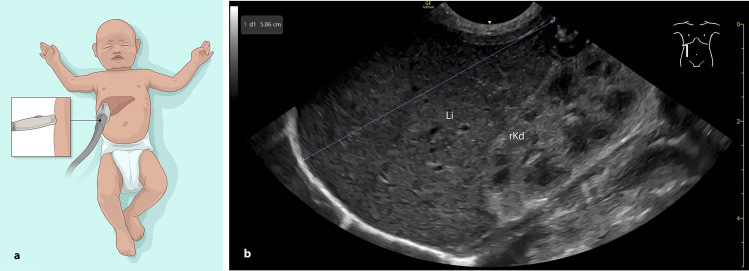

Purpose: In term and preterm infants, liver size is important for assessing growth and detecting conditions such as hepatomegaly, infections, or cardiac failure. The German Society for Ultrasound in Medicine (DEGUM) recommends measuring craniocaudal liver length in two frontal planes: the midsternal line (MSL) and the right anterior axillary line (AAL). This study evaluated whether liver length measurements in the right AAL from a lateral view yield results comparable to the standard frontal view, as the lateral approach may be technically more accessible and less stressful for neonates.

Material and methods: In this prospective single-center study conducted in a level III neonatal intensive care unit, 62 term and preterm infants underwent 107 liver measurements between July and December 2024. Each measurement was performed in both the frontal and the alternative lateral AAL plane. Statistical analysis included Wilcoxon matched-pairs signed rank test, Pearson Correlation Coefficient, and Bland-Altman analysis.